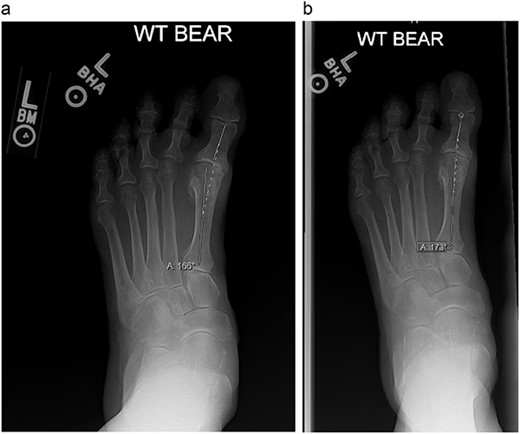

An 84-year-old female presented in clinic with acquired hallux varus of the left foot. She reported that the deformity had been symptomatic for 4 years and that her pain was exacerbated with standing. At the time of presentation, it measured 14° on weight bearing radiographs (Fig. 4A). The deformity was flexible but recurred once the correcting force was removed. The patient had no tendon dysfunction and normal muscle function in the lower extremity. Taping her toe had provided symptomatic relief, but the deformity returned with tape removal. The patient wished to avoid surgery and the use of botulinum toxin for correcting her deformity was proposed by a family member who was a retired orthopedist. After shared decision making, it was agreed that weakening of the AHB with botulinum toxin to reduce the putative deforming force was a reasonable strategy to provide symptomatic relief as well as offer temporary correction to avoid operative treatment. She understood that botulinum toxin injection, if successful, would likely need to be repeated indefinitely.

(a) and (b) are weight-bearing radiographs with angle measurements of the amount of hallux varus at the first MTP joint.

The patient had repeat injections every 3 months, which is customary with botulinum toxin injections as an accepted length in duration of action [6]. Each injection gave symptomatic relief for close to 12 weeks with near total resolution of pain and resumption of activities of daily living. There was no additional adjuvant therapy such as physical therapy, stretching, taping or bracing required. The radiographic correction seen was improvement from 14° to 7° on weight bearing radiographs (Fig. 4B). At her most recent follow-up, the patient reported some pain on the medial aspect of her first toe when in dress shoes but was pain free at the MTP joint when walking barefoot or in walking shoes. Currently, the patient has had five injections with consistency in efficacy and no adverse reactions.